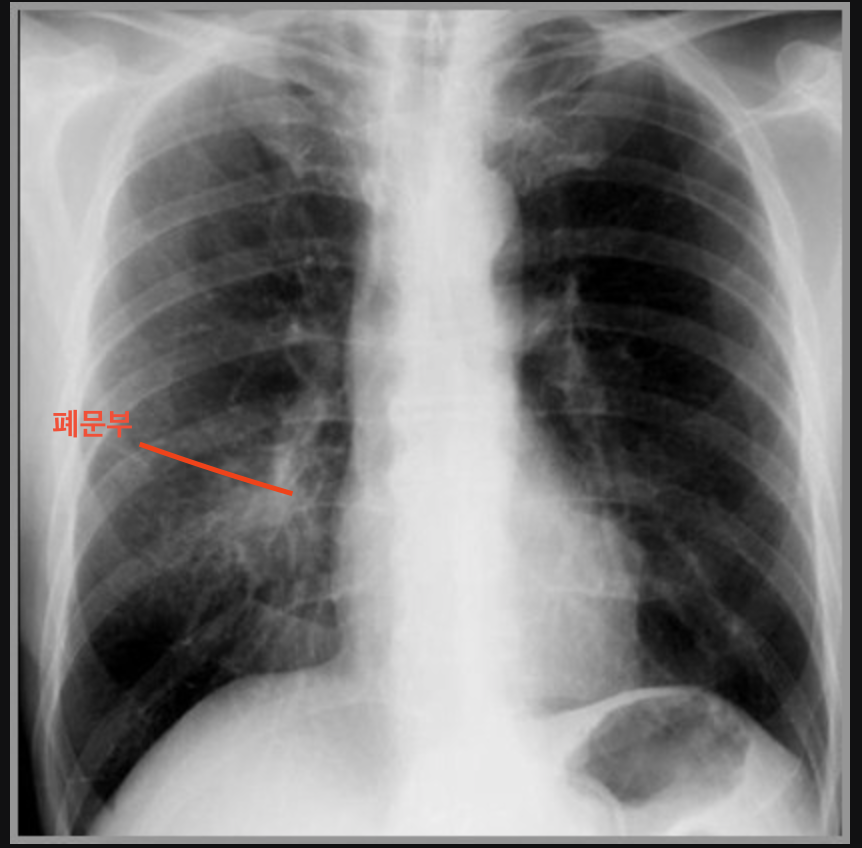

마이코플라즈마 폐렴은 마이코플라즈마라는 세균에 의해 발생하는 폐렴의 일종입니다. 이 세균은 일반적인 세균과는 달리 세포벽이 없어서 항생제에 대한 내성이 강한 특징이 있습니다. 주로 기침이나 재채기를 통해 전파되며, 감염된 사람의 호흡기 분비물에 의해 쉽게 전염됩니다. 특히, 어린이와 청소년, 면역력이 약한 노인층에서 자주 발생합니다.